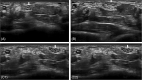

Median nerve instability in the wrist: Ultrasound diagnosis

Instability of the nerves, which does not follow traumatic injury, is relatively rare. The ulnare nerve is most typically involved. Median nerve instability is far less common. The identification of instability of the median nerve in the wrist is definitely an indication for ultrasound examination before carpal tunnel release.